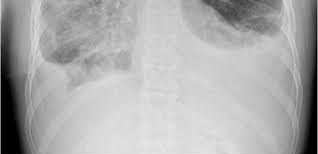

Lymphangiomatosis is difficult to diagnose since it is unusual and possesses a vast range of imaging, clinical, and histological characteristics. Plain x-rays are enough to show lytic tumors in chylous effusions, bones, pathological fractures, and interstitial infiltrates in the lungs, even if no indications are evident.